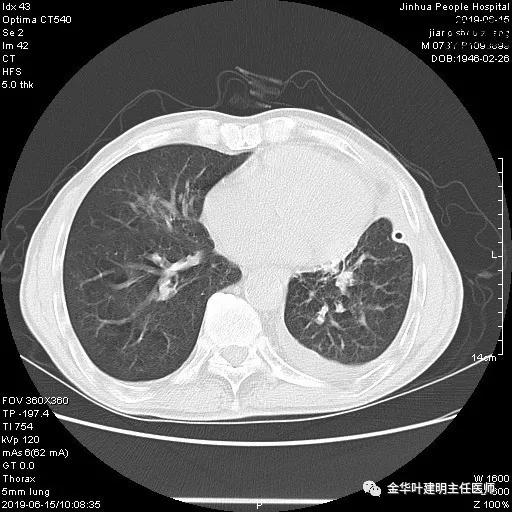

考虑左侧大量胸腔积液,遂进一步胸部CT检查:

以上是肺窗表现,下面为纵隔窗影像: